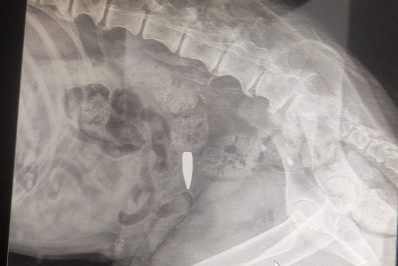

Segundo a delegada Márcia Helena Julião, a criança apresentava 59 lesões pelo corpo, entre já cicatrizadas e recentes: 17 no abdômen, 16 no dorso, 12 no rosto, 7 nas pernas e 6 nos braços. Ainda de acordo com ela, a Polícia Civil foi acionada após receber a denúncia de uma médica da Clínica da Família Hans Jurgen Fernando Dohmann, em Guaratiba, que relatou que a garota, trazida pelo pai, apresentava "sinais severos de violência", como queimadura no umbigo e fissura no ânus. A criança também não teria sido alimentada há, pelo menos, três dias.